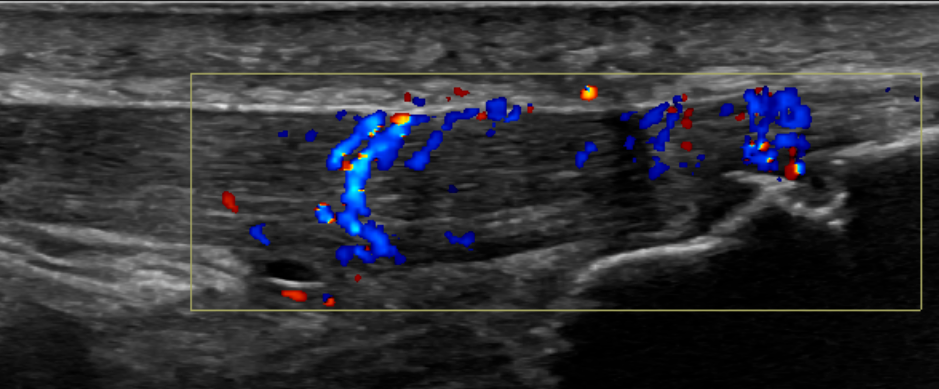

3. Patellar tendinopathy